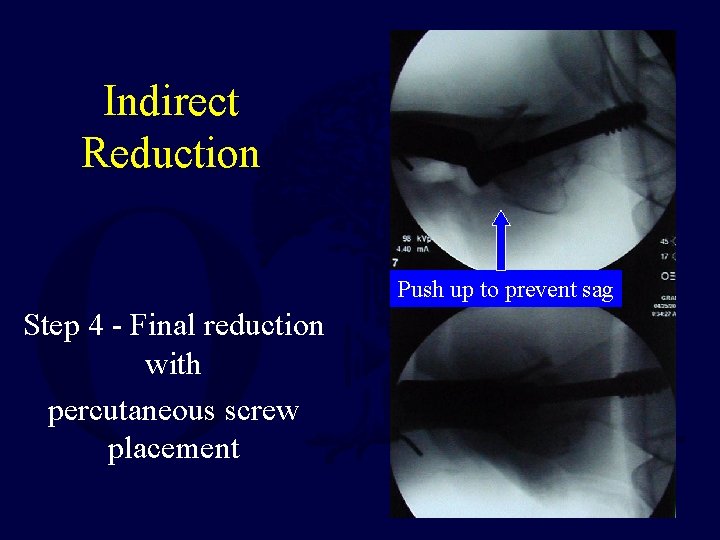

Indirect Reduction Push up to prevent sag Step 4 - Final reduction with percutaneous screw placement